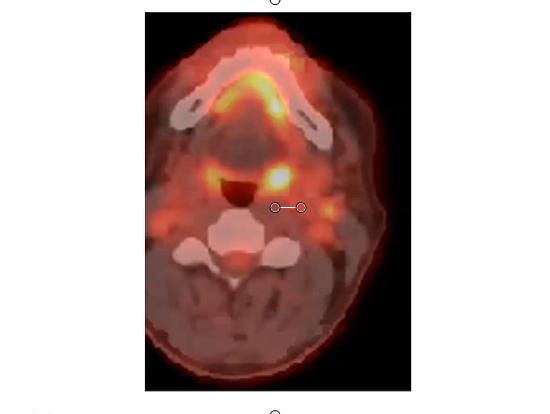

retropharyngeal lymph node, supraclavicular nodes, PET, dosimetry, GTV, QUAD SHOT, CPS, non metastatic, immunotherapy, sinonasal carcinoma